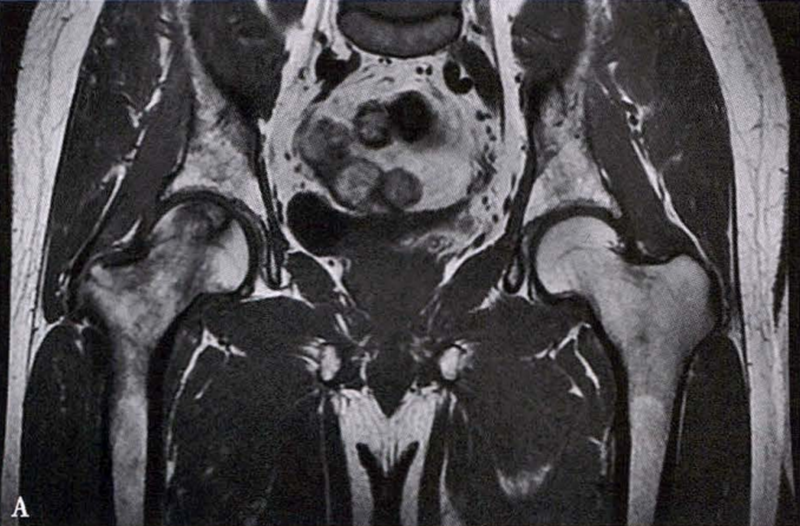

(2)MRI检查 MRI检查是早期诊断股骨头坏死最具特异性、灵敏度的检查方法。当怀疑有股骨头坏死,而X线片无明显异常时,应行MRI检查。诊断时可根据髋关节X线、MRI显示的坏死面积和塌陷程度进行ARCO分期。

冠状面及横断面MRI图像

MRI示双侧股骨头坏死,冠状面显示右侧股骨头坏死(图A、C),横断面显示双侧股骨头坏死(图B、D);T1加权像(图A、B)显示硬化带为低信号,T2加权像(图C、D)显示右侧骨坏死硬化带外围高信号的骨髓水肿,左侧无骨髓水肿。